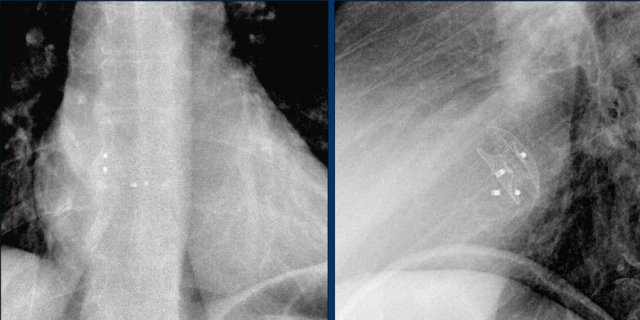

Epicardial pacing leads

Epicardial leads are frequently placed during cardiac surgery in order to allow cardiac pacing post-surgery.

Some centers place them in all cardiac surgery patients, while others only in those who have rhythm disturbances intra-operatively.

After a few days they can be removed by simple traction.

Sometimes they are left in place.

Retained epicardial wires do not seem to present a hazard to patients in the MR environment.

However, this conclusion applied mostly to non-cardiac MR examinations.